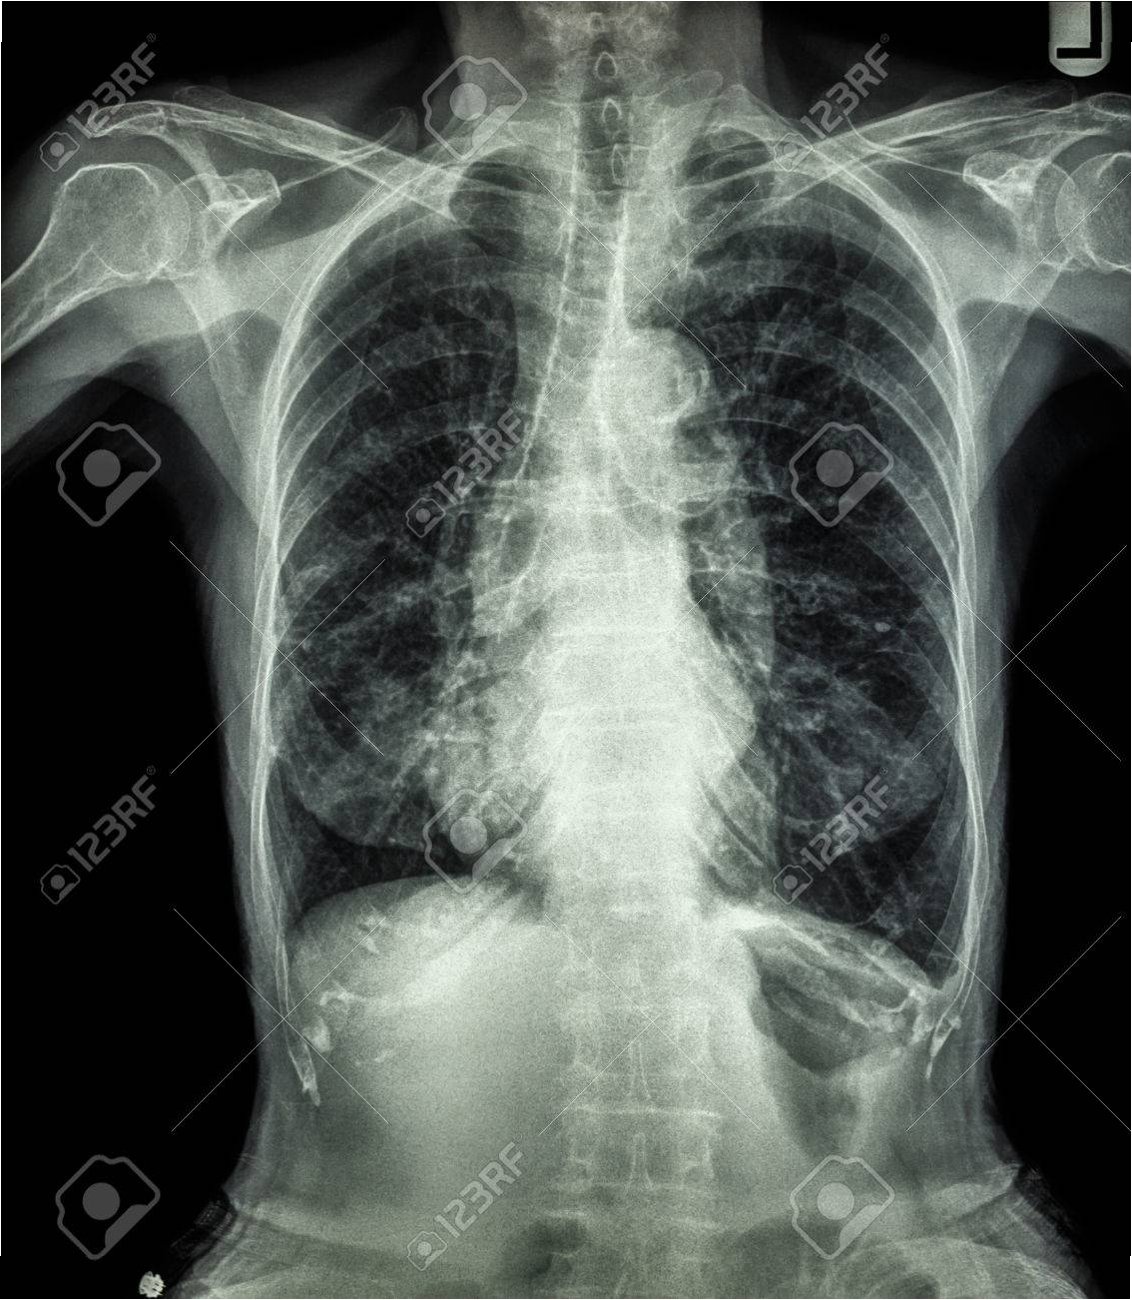

2019년부터 시작된 원인 불명의 밤마다 반복되는 고열로 병원을 찾은 사이먼스 씨는 CT 검사 결과 충격적인 사실을 마주했습니다. 사고 당시 폐 깊숙이 들어간 먼지 파편이 체외로 배출되지 못한 채 딱딱하게 굳어 왼쪽 폐 기관지를 완전히 막고 있었던 것입니다. 그는 “기계에 깔려 움직일 수 없을 때 먼지를 들이마셨는데, 그게 깊이 들어가 굳어버렸다”고 당시 상황을 설명했습니다. 의료진은 외상으로 인해 체내에 남은 이물질이 장기간에 걸쳐 칼슘으로 둘러싸여 석회화가 진행된 것으로 판단했습니다. 정밀 검사 결과, 좌측 폐는 5년간의 감염으로 기능을 완전히 상실한 상태였습니다.

의료진은 처음에는 석회화된 부분만 제거하려 했으나, 손상 범위가 너무 넓어 폐 전체를 적출해야 한다는 결론에 이르렀습니다. 사이먼스 씨는 결국 왼쪽 폐를 떼어내는 수술을 받았습니다. 그는 “작은 먼지 한 톨이 내 인생을 이렇게 바꿀 줄 몰랐다”며 “수술 동의서에 서명하던 순간이 인생에서 가장 무거웠다”고 심경을 토로했습니다. 이처럼 외상으로 체내에 남은 이물질은 장기간에 걸쳐 석회화되며 염증이나 조직 괴사를 일으킬 수 있습니다. 특히 폐 조직은 통증 수용체가 적어 초기 증상 인지가 어렵고, 뒤늦게 발견되는 경우가 많아 주의가 필요합니다.